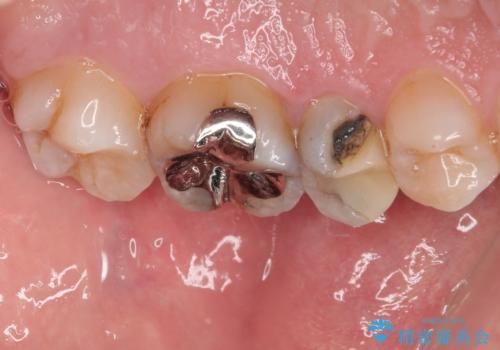

まず、虫歯を丁寧に除去。

欠損範囲が大きかったため、オールセラミッククラウンによる補綴治療を行いました。

「他の歯も、せっかくなら精度の良いものに替えておきたい」とのご希望があり、

上顎左側第一大臼歯

下顎左側第一大臼歯

に入っていた保険診療の銀歯(メタルインレー)を、精度の良いゴールドインレーへやり替えを行いました。